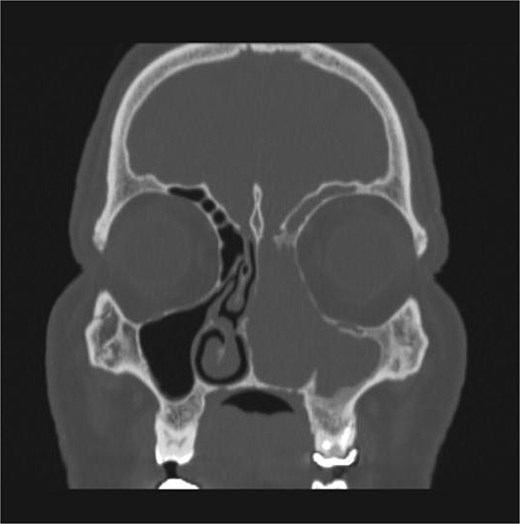

The patient underwent staging CT which was negative for distant metastasis. He then went underwent incomplete medial maxillectomy, ethmoidectomy, and sphenoidotomy followed by 10 sessions of immunotherapy abroad. He presented to our institution for follow up 6 months later with history of left nasal block and epistaxis. Nasal flexible scope showed a reddish nasal mass with greenish secretions (Fig. 3). Follow up CT revealed tumor recurrence (Figs 4 and 5). He was advised for multidisciplinary team evaluation to plan the treatment but he refused any intervention and lost follow up.

Coronal section of CT paranasal sinus bone window showing bony erosions of nasal septum, maxillary wall, lamina papyracea, and cribriform plate.